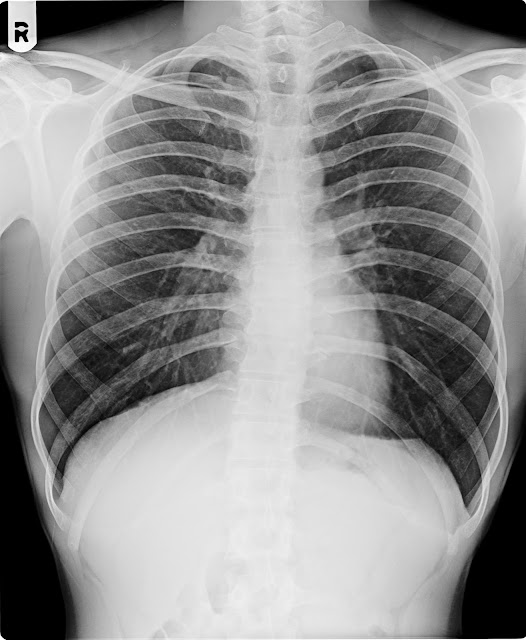

X-RAY CHEST PA VIEW.

Both lung fields appears normal.

No evidence of koch’s lesion or consolidation seen.

Both apices, cardiophrenic, costophrenic angles and domes of the diaphragm are normal.

The cardiac size is within normal limit.

Trachea is central, no mediastinal shift is seen and the mediastinal outlines do not show any

abnormality.

Bony thorax appear normal

IMPRESSION ; NORMAL